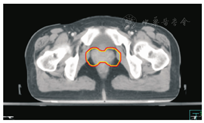

笔者所在科室对于FIGO临床分期为ⅡB期宫颈癌(阴道穹窿受侵、宫旁受侵近盆壁)的调强放疗流程及靶区CTV勾画范围建议如下。对其定位前准备工作包括:患者于定位前30~40 min排空膀胱,再饮水500 mL(含造影剂碘化醇10 mL),显影小肠。对其靶区CTV勾画具体操作步骤为:让患者取仰卧位,身下垫胸、腹平板,双手抱肘并上抬置于额头,热塑体膜固定(上腹至大腿上约1/3处);待热塑体膜冷却成形后,激光灯下于体前正中和两侧分别置铅点(尽可能靠近靶区中心)。此时尽可能行CT增强扫描,以更清楚显示解剖位置;对造影剂过敏、高龄、伴有严重并发症等不适合行CT增强扫描者,仅进行平扫。CT检查的扫描范围为:第一腰椎体上缘至坐骨结节下2 cm,层厚为5 mm,若腹主动脉旁淋巴结转移,则上移至隔顶;若全阴道浸润、腹股沟淋巴结转移,则下移至外阴下4 cm。其中,对靶区CTV勾画:放疗前,应常规实施CT、MRI或PET-CT检查,以明确肿瘤靶区范围及是否存在远处转移(部分远处转移病变,可与原发部位同时进行放疗)。对于其GTV勾画,则包括临床肉眼可见或可触及的,或可通过检查手段证实的肿瘤区域,具体包括宫颈肿瘤、受侵宫旁及阴道组织。MRI检查是确定软组织及宫旁受侵的较理想方法。若腹膜后淋巴结转移,需对淋巴结照射剂量进行加量时,CTV则应单独勾画转移淋巴结靶区。CTV勾画分为局部肿瘤区域和淋巴引流区域。局部肿瘤区域CTV勾画,包括局部肿瘤GTV及显微镜下可见的亚临床肿瘤病变,首先为宫颈、宫体、宫旁和阴道CTV勾画。①宫颈CTV:勾画全部宫颈。②宫体CTV:勾画全部宫体。③宫旁CTV:勾画上界为乙状结肠跨过子宫及输卵管处,下界为泌尿生殖膈,前界为膀胱后壁/髂外血管后缘。若子宫前倾明显,则子宫前界为宫旁前界,后界为宫骶韧带和直肠系膜前缘,内侧界为子宫颈阴道,外测界为骨盆壁,不包括肌肉和骨。值得注意的是:若宫骶韧带受累,CTV勾画则需将整个宫骶韧带全部包括在内,此时直肠系膜淋巴结及直肠周淋巴结均应包括在内。对于FIGO临床分期为ⅢB期及以上者,CTV应将直肠周淋巴结勾画在内,宫旁靶区与髂淋巴结及闭孔淋巴结区重叠。④阴道CTV:若阴道无受侵,则勾画阴道上段1/2,若上段受侵,则勾画阴道上段2/3,若阴道广泛浸润,则勾画全阴道。其次,盆腔淋巴结引流区包括宫颈旁、宫旁、闭孔、髂内、髂外、骶前及髂总淋巴结CTV勾画,依照其血管走行进行勾画。①髂总动脉CTV:上界为腹主动脉分叉下缘,下界为髂总动脉分叉下缘;前界为血管前7 mm,后界为血管后7 mm;内侧界为血管内侧7 mm,外侧界为血管外7 mm,腰大肌内侧缘,包括腰大肌与椎体旁间隙。②髂外动脉CTV:上界为髂总动脉分叉下缘,下界为股骨头上缘即股动脉;前界为血管前7 mm,后界为血管后7 mm;内侧界为血管内侧7 mm,以子宫、卵巢、肠管、输尿管及膀胱为界,外侧界为血管外7 mm,腰大肌及髂腰肌内侧缘。③髂内动脉CTV:紧邻髂内血管及其分支,上界为髂总动脉分叉下缘,下界为尾骨肌上缘、坐骨棘或子宫动静脉上端;前界为血管外7 mm,后界为上部以骶骨翼为准,中下部至梨状肌前缘或臀下动静脉;内侧界为血管外7 mm,外侧界为头侧髂腰肌、髂肌或骶髂关节外侧,中间为髂骨、髂腰肌或髂肌内侧缘;尾侧界为闭孔内肌或梨状肌内侧。④闭孔淋巴结CTV:上界为骶髂关节下缘连接至髂内淋巴结,下界为闭孔上缘;前界为上中部分连接到髂外,下部至耻骨后缘,后界上中部连接到髂内,下部至闭孔内肌后缘;内侧界至膀胱、子宫及肠管,沿骨盆壁向内扩18 mm,外侧界至闭孔内肌、髂肌、髂腰肌或髂骨。⑤骶前淋巴结CTV:上界为髂总分勾画范围,见图1,图2,图3,图4,图5,图6。